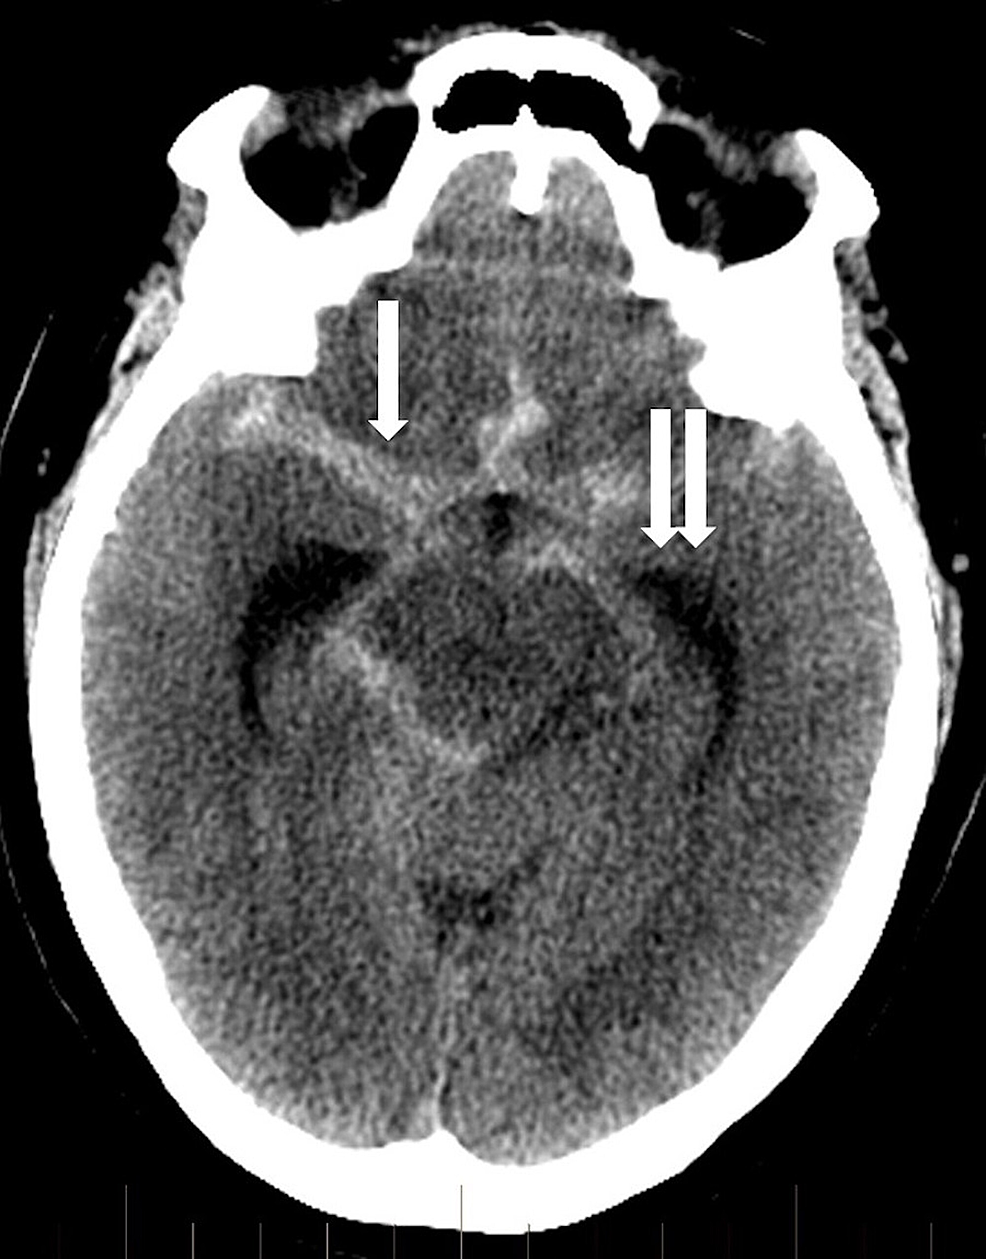

Complications of endovascular aneurysm treatment aneurysm rupture. (A Coiling Aneurysm Rupture In the 1990s, coiling was introduced as a way of treating ruptured and unruptured brain aneurysms without the need for a craniotomy (an operation that opens the skull to expose the brain). the cerebral aneurysm rupture after treatment (carat) trial examined 1010 unselected patients with. coiled aneurysms with class iiib recanalization should undergo early retreatment because of an. Coiling Aneurysm Rupture.